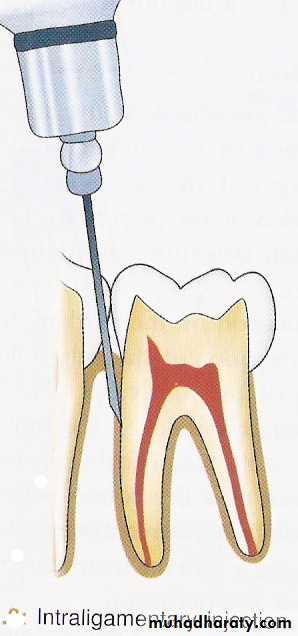

If anaesthesia is required in the lower premolars, canine and incisor, then other alternative techniques such as mental nerve block, periodontal ligament injection, intraosseous anaesthesia and intrapulpal injection are given.

10